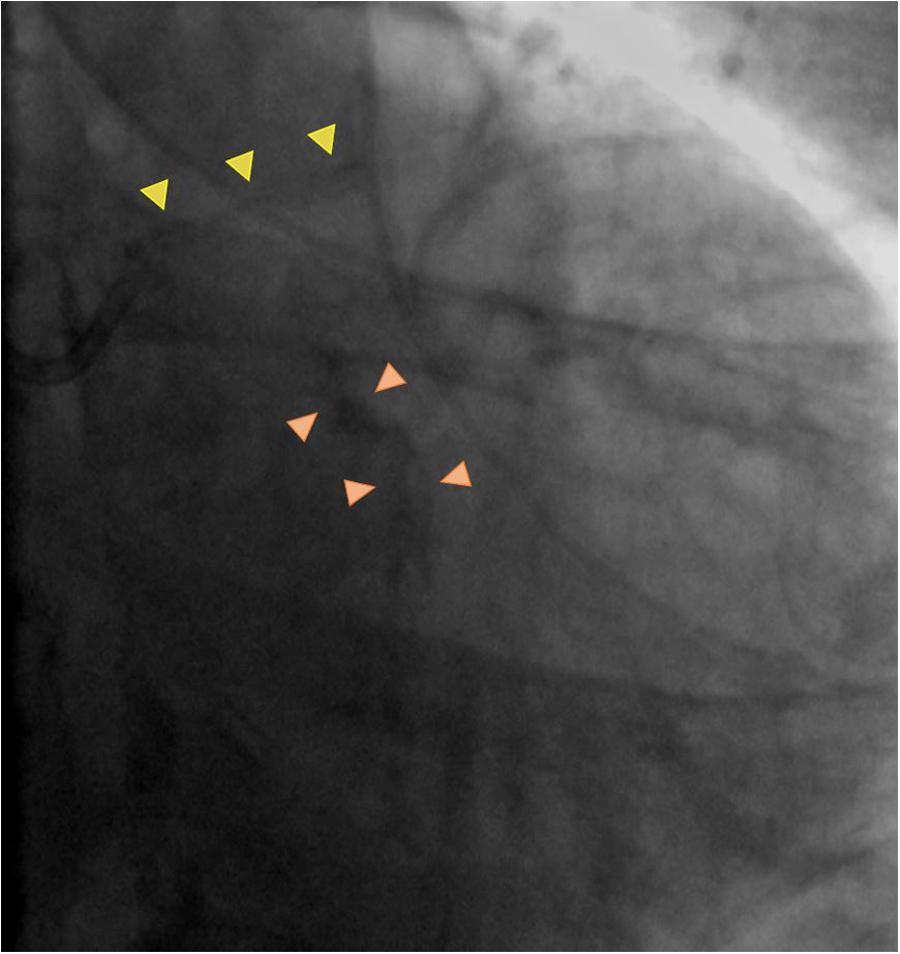

Coronary angiography has historically been the first modality used to detect CAC. On angiogram, CAC can be visualized as areas of linear x-ray attenuation along the course of a coronary artery (Figure 2). Angiography presents good specificity for CAC, however, in Mintz et al., coronary angiography had a diagnostic accuracy of about 38% (with 26% of those lesions having moderate CAC and 12% having severe CAC), which was corroborated in a more recent study by Wang et al. indicating an accuracy for coronary angiography of about 40.2% when compared to IVUS (8, 10). When assessing the ability of angiography to detect CAC patterns, the diagnostic accuracy increases when calcium eccentricity is >180°, length is >6 millimeters (mm), and superficial calcification is present, and accordingly, with lesser degrees of eccentricity, lower calcification length, and presence of deep calcium, accuracy falls to below 50% (8).

Figure 2

Coronary angiography calcification pattern summary. Calcium appears as gray or black outlines, easily assessable when no contrast dye is injected and which follow the coronary artery silhouette, with position excursion in line with vessel movement during the cardiac cycle. Mild calcification is defined as appearance of the calcified component only on one side of the vessel (yellow arrowheads), whilst severe calcification is defined as appearance of the calcified component on both sides of the vessel.